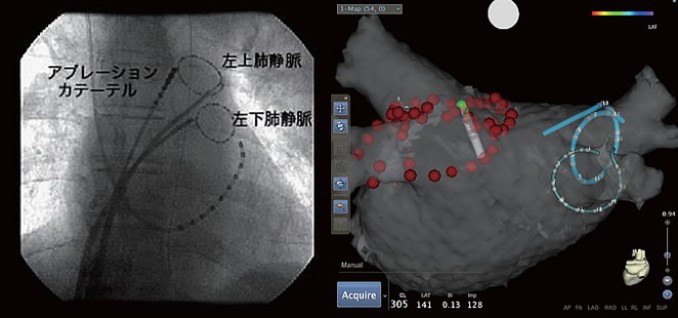

図のように上下の肺静脈にリング上カテーテルを留置し、このカテーテルの情報をもとに肺静脈周囲の焼灼を行っていきます。近年は3Dマッピングシステムを利用して、透視時間が減少し、効率よく正確にカテーテルアブレーションが施行可能となってきています。最終的に4本の肺静脈と左房との電気的な交通が途絶えたことを確認して治療は終了となります。治療終了後は止血のためベッド上で6時間の安静を要します。